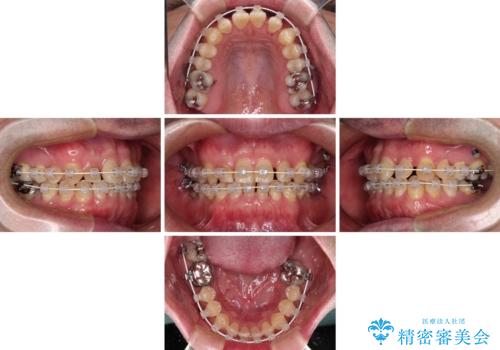

矯正治療は、ワイヤー装置とマウスピース矯正との選択肢がありましたが、マウスピース矯正は自己管理が煩わしいことを気にされて、目立たないワイヤー装置にて行うこととしました。

インプラント埋入による仮歯の装着や、前歯の反対咬合の改善は比較的スムーズに達成されましたが、舌突出癖などの影響による、歯列全体のスペースを閉じることが難航し、期間がかかってしまいました。

治療後も舌突出癖が残っていると、あっという間にスペースができてしまうので、トレーニングを継続するように指導をしています。